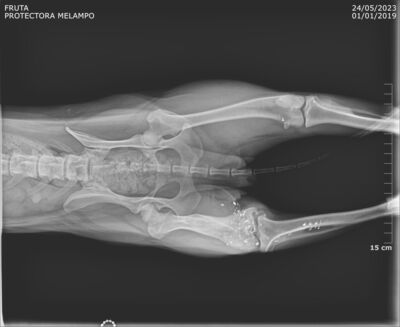

Fruta wurde kastriert und ihr alte Verletzung wurde dabei auch gleich geröngt. Dabei kam heraus, dass Fruta eine Schussverletzung hat und immer noch Schrot im Bein hat. Die Röntgenbilder sind weiter unten zu finden.

Fruta’s Hinterbein wurde beim Spezialisten abgeklärt. Das Bein ist steif, sie hat aber keine Schmerzen. Es stört sie auch nicht, sie läuft, rennt und hüpft auch ohne Probleme aufs Sofa.